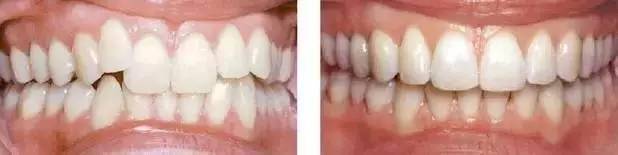

- 说到牙齿矫正费用大概多少,很多人只能说出与患者的牙齿状况有联系,其实牙齿矫正费用还与年龄有关。一般来说,孩子做牙齿矫正相对较简单, 报价也会低一点,成年人由于矫正难度稍大,费用会相对高点。那么牙齿矫正目前的费用大概多少?

康贝佳口腔医生说,牙齿变形的程度,有的仅仅牙齿的畸形,有的是牙列不齐,牙齿稀少、龅牙等状况,这么就致使牙齿矫正的难度不一样使的牙齿矫正多少钱也不 一样。

牙齿矫正多少钱与求美者所选用的牙齿矫正的办法有关:不一样的办法,报价是不一样的,目前最廉价的即是传统的金属钢丝牙齿矫正,还有半 隐形的陶瓷托槽矫正技能,自锁托槽隐形矫治技能,不一样的办法对应的牙齿矫正多少钱也是不一样的。